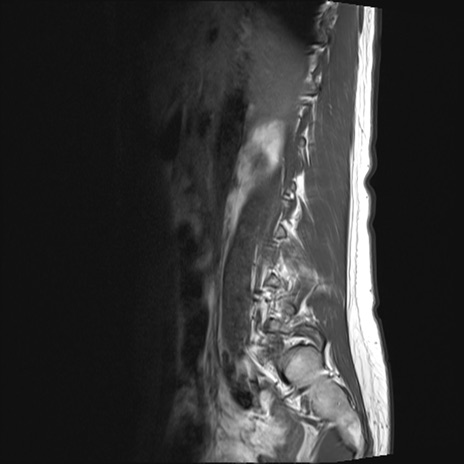

【整形】TIPS症例4 腰椎MRI T1WI(矢状断像)

腰椎MRI

STIR(矢状断像)